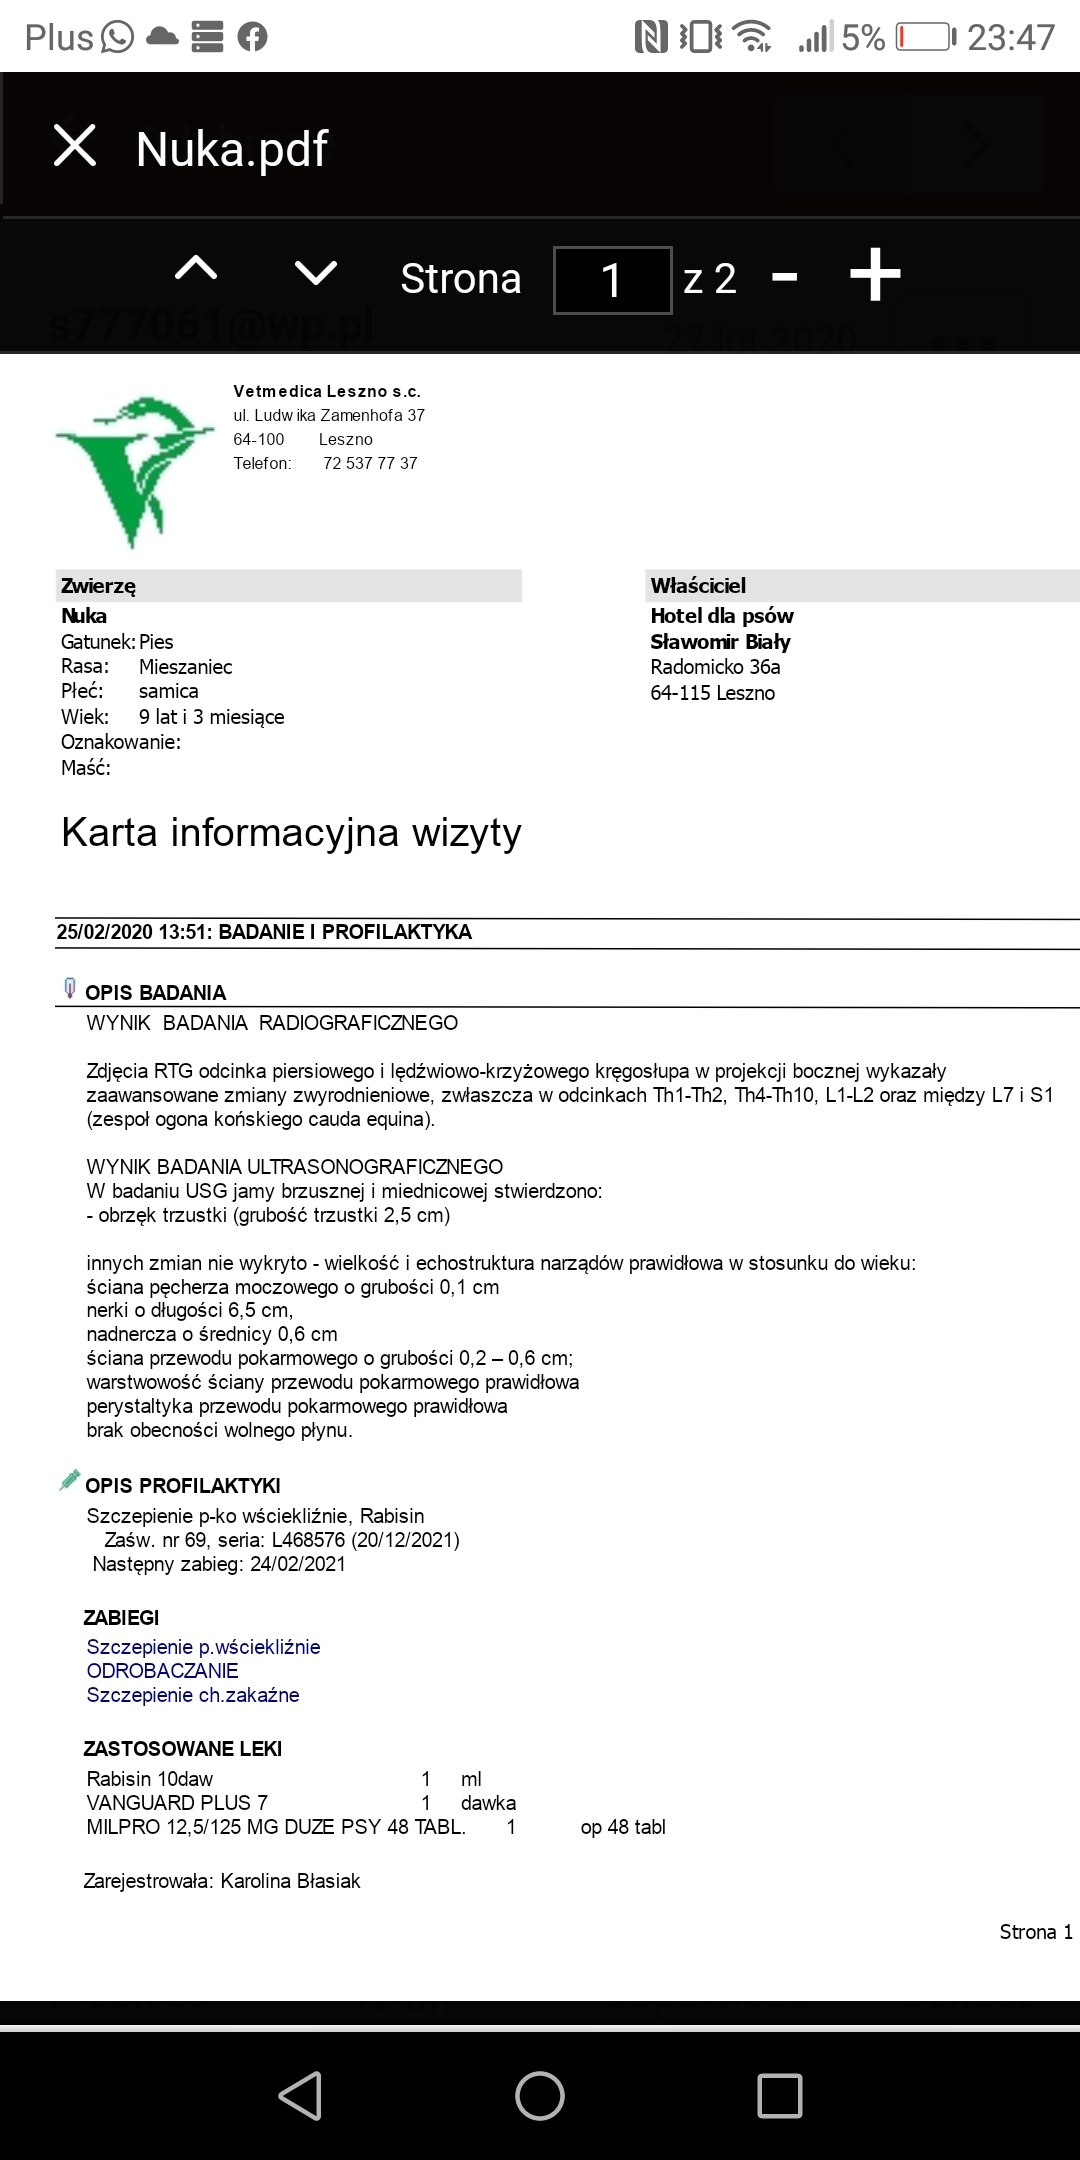

Kochani ta zbiórka jest założona na utrzymanie i leczenie suni Nuki zabranej z fatalnego przytuliska do hotelu by nie trafiła do schroniska. W hotelu przebywa już prawie 4 lata. Jest już starsza sunia... Takie psiaki maja małe szanse na adopcję. Dodatków problemem Nuki było nieakceptowanie małych dzieci. Nie mogliśmy jednak pozwolić by zginęła w schronisku. Czas nie oszczędza jednak Nuki i poglebily się problemy zwyrodnieniowe oraz doszło zapalenie trzustki. Nuka by żyć bez bólu musi dostawać lek o nazwie cimaglex 80 mg. Miesięczny koszt leczenia to 200 zł. Do tego musi jeść karmę niskotłuszczowa dla trzustkowcow. Koszt karmy takiej weterynaryjnej to ok. 250 zł.